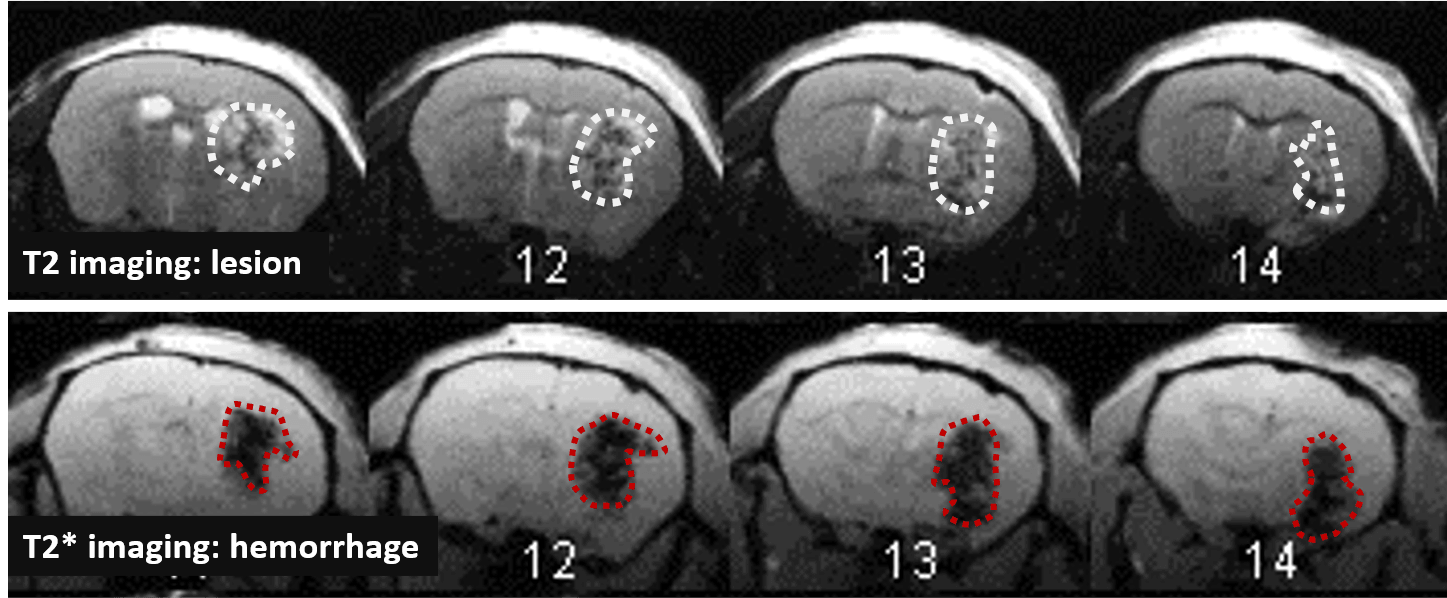

Changes in the volume of both the lesion (T2) and the haematoma (T2*) can be located, measured and tracked with MRI brain imaging. (Illustration: Figure 1: rat on day 1 , Figure 2: mouse on day 1).

Long term monitoring enables researchers to highlight the impact of a treatment over the longer term and to observe the animal’s functional recovery phase (Figure 3). It also makes it possible to track the reduction in post-induction oedema and tissue remodelling in the damaged area. The activation of those processes results in a reduction in the size of the lesion (phagocytosis of cellular debris, glial colonisation, etc.).

In the study of our ICH model, we assessed the impact of an anticoagulant agent (such as Enoxaparin). We observed that Enoxaparin produced an increase in the volume of the haemorrhage at day 1 (Figure 4) as well as an increase in the size of the lesion at day 3 (Figure 5). With this model it is possible to assess a susceptible molecule’s risk of bleeding to provoke over bleeding.

By using MPIOs coupled with a V-CAM1 antibody, we have been able to quantify in vivo the impact of Enoxaparin pre-treatment on the expression of this cell adhesion molecule and thus demonstrate the level of post-haemorrhage inflammation (Figures 4 and 5).

and VCAM quantification at D3 (on the right), hemispheres comparaison (ANOVA; *p<0.05; Mean +/- SEM); Effect of Enoxaparin VS PBS (ANOVA; *p<0.05) H= hemisphere